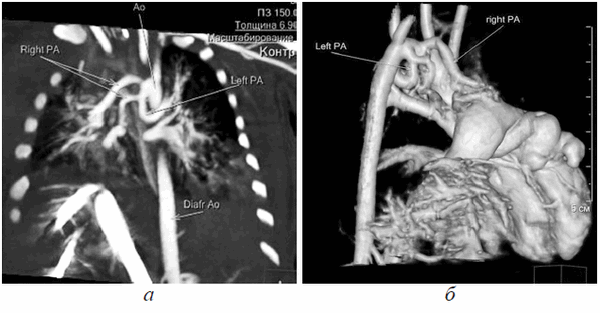

Ребенок был осмотрен коллегией специалистов: неонатологом, кардиологом, кардиохирургом, торакоабдоминальным хирургом, неврологом. Состояние ребенка расценено как стабильное, тяжелое, сознание на момент осмотра медикаментозно угнетено. При поступлении пациентке выполнена обзорная рентгенограмма грудной и брюшной полостей, визуализирующая сердечную тень в проекции эпигастрия, что дало представление о эвентрации сердца на переднюю брюшную стенку, однако не отражало анатомию внутрисердечных структур. Верхняя доля правого легкого ателектазирована, в дистальных отделах обоих легких выявлены признаки интерстициального отека легочной паренхимы. Контуры диафрагмы четкие, ровные (рис. 2). Учитывая отсутствие возможности проведения трансторакального ЭХО-КГ, в силу отсутствия кожно-апоневротического компонента, покрывающего сердце, в рамках предоперационного планирования принято решение о выполнении мультиспиральной компьютерной томографии (МСКТ) области грудной клетки с целью определения анатомии внутрисердечных структур и определения типа врожденного порока сердца.

Рис. 2. Обзорный ренгтеновский снимок, показывающий атипичную локализацию сердечной тени, асимметричное положение диафрагмы, неравномерную пневматизацию легочной ткани

Девочке 2-х суток жизни выполнена МСКТ в условиях медикаментозной седации с проведением проспективной ЭКГ-синхронизации, болюсного внутривенного контрастирования (в/в) препаратом Визипак 270 в объеме 6 мл в периферическую вену правой нижней конечности. Сканирование осуществлено на аппарате Philips Ingenity 128, kv 80, mas 350, протяженность сканирования 250 мм. Выполнено обзорное сканирование грудной клетки и брюшной полости до контрастного усиления, по результатам которого определяется диффузная неравномерность пневматизации легочной паренхимы, с наличием участков ателектазированной легочной ткани в верхних и нижних долях легких с обеих сторон, в обеих плевральных полостях определяется умеренное количество выпота (рис. 3). Сердце визуализировано вне грудной полости (рис. 4). В грыжевом мешке определяется фрагмент паренхиматозного органа брюшной полости, по нативным денситометрических показателям идентичный паренхиме печени (50HU), как показано на рисунке 5.

Рис. 3. Мультиспиральная компьютерная томография, мультипланарная реконструкция (MPR) легких в корональной проекции, в просвете трахеи интубационная трубка, пневматизация легких диффузно неравномерная с наличием участков ателектазированной легочной ткани

Рис. 4. Мультиспиральная компьютерная томография (МСКТ) легких, аксиальная проекция, патологический выпот в обеих плевральных полостях, эктопия сердца на переднюю грудную стенку

Рис. 5. МСКТ брюшной полости, аксиальная проекция, визуализирован грыжевой мешок, содержащий правую долю печени

После в/в контрастрования сканирование произведено в двух направлениях — каудокраниальном и краниокаудальном с целью визуализации анатомии сердца, определения сопутствующих пороков. В первую очередь требовалось уточнение анатомии камер сердца. По результатам исследования визуализированы полости правого и левого желудочков (ПЖ и ЛЖ), разделенные межжелудочковой перегородкой, с наличием дефекта в подклапанном отделе.

Правосторонняя предсердно-желудочковая конкордатность сохранена, анатомия правого предсердия определена наличием впадающего в него устья нижней полой вены. Левосторонняя внутрисердечная конкордантность оставалась под сомнением, так как ЛЖ сообщался с полостью, не имеющей в своей анатомии устьев легочных вен (рис. 6). Анатомия магистральных артерий также не являлась типичной. На (рис. 7, а) отчетливо визуализируется сформированный выходной тракт ЛЖ, корень аорты (Ао) с отходящими от лицевых синусов коронарными артериями, восходящий отдел Ао, дуга Ао с отходящими от нее брахиоцефальными сосудами, нисходящий отдел грудной Ао. Размеры всех вышеуказанных отделов магистральной артерии соответствовали росто-весовым показателям новорожденной (рис. 7, б).

Рис. 6. МСКТ, МPR. Четырехкамерная позиция, правосторонняя предсердно-желудочковая конкордантность сохранена, левосторонняя сомнительна

Рис. 7. МСКТ, сагиттальная проекция. (а) Визуализирован выходной тракт ЛЖ, сформированный корень Ао, восходящий отдел Ао, дуга Ао, нисходящий отдел Ао; МСКТ, объемная реконструкция (3D-volume rendering) сердца (б)

Источник кровоснабжения малого круга кровообращения в виде наличия легочной артерии (ЛА) отсутствовал, выходной отдел ПЖ не сформирован, правосторонняя предсердно-артериальная конкордантность нарушена. При детальной оценке полученных изображений визуализированы артериальные сосуды, отходящие от дуги Ао и направляющиеся к легким с обеих сторон. Общее количество больших аортолегочных коллатералей (БАЛК) — 2 (рис 8, а, б).

Рис. 8. МСКТ, MPR, определяются БАЛКи к правому и левому легким (а); МСКТ, 3D volume rendering, визуализация БАЛК к легким (б)

К правому легкому определено наличие двух ветвей БАЛК, одна из которых самостоятельно отходит от дуги Ао, вторая является ветвью БАЛКи, идущей также от дуги Ао, но имеющей деление на правую и левую ветви к одноименным легким соответственно. При анализе анатомии левого предсердия (ЛП) типичного расположения легочных вен (ЛВ) не отмечалось. Полость, сообщающаяся с ЛЖ, вбирала в себя единый венозный коллектор ЛВ, в который дренировались ЛВ обоих легких. Таким образом, был сделан вывод о том, что полость сообщающаяся с ЛЖ и включающая в себя единый венозный коллектор ЛВ, является ЛП (рис. 9). Анализируя структуры МПП и МЖП, отмечались множественные дефекты перегородок.

Рис. 9. МСКТ, аксиальная проекция, показан единый коллектор легочных вен

По результатам проведенного исследования было сделано заключение о наличии у пациента врожденного порока сердца — атрезия ЛА IV типа, БАЛКи ДМПП, ДМЖП, единый коллектор ЛВ в условиях эктопии сердца.